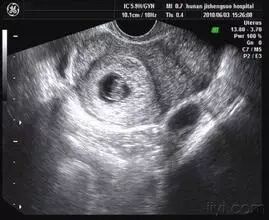

到怀孕六个多月时,突然出血了,量还很大。她的丈夫吓坏了,赶紧把她送到了医院。检查结果让她不敢相信——B超检查显示,子宫内充满了水泡状的东西,就跟葡萄一样,根本没有胎儿。

原来,这怀的是葡萄胎!医生说,它是指妊娠后胎盘绒毛滋养细胞增生,间质高度水肿,形成大小不一的水泡,水泡间相连成串,形状就像葡萄一样。发病率大约为1/1000。换句话说,就是胎儿没正常发育。

葡萄胎是指妊娠后胎盘绒毛滋养细胞增生,间质高度水肿,形成大小不一的水泡,水泡间相连成串,形如葡萄,亦称水泡状胎块(HM)。

葡萄胎分为两类:①完全性葡萄胎 胎盘绒毛全部受累,整个宫腔充满水泡,弥漫性滋养细胞增生,无胎儿及胚胎组织可见;

②部分性葡萄胎 部分胎盘绒毛肿胀变性,局部滋养细胞增生,胚胎及胎儿组织可见,但胎儿多死亡,有时可见较孕龄小的活胎或畸胎,极少有足月婴诞生。